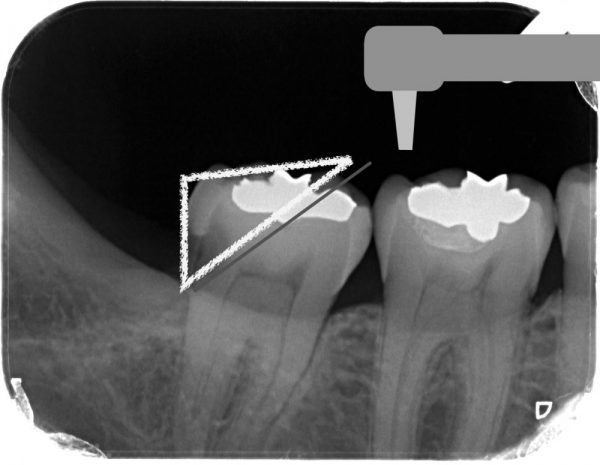

親知らずはすでに抜いていますが、虫歯が進行しています。歯の内部に黒い線がありますが、これは神経の管です。神経の管の近くまで虫歯がきています。 一般的な虫歯治療だと、このように道具は前からしか入れることはできないので、大きく歯を削ることになります。虫歯は奥の黒いところだけなのに上部の健康な歯も大きく削ることにもなります。

一般的な虫歯治療だと、このように道具は前からしか入れることはできないので、大きく歯を削ることになります。虫歯は奥の黒いところだけなのに上部の健康な歯も大きく削ることにもなります。

しかも、神経の管を傷つけることも多く、神経をとる場合もあります。大きく歯を削ると神経をとるリスクも増えます。

当院ではマイクロスコープを使用し、特殊な超音波のチップなどを駆使して直接虫歯だけを削り取ります。

当院ではマイクロスコープを使用し、特殊な超音波のチップなどを駆使して直接虫歯だけを削り取ります。

このようにアプローチすることで、健康な歯と神経を残して、かつ虫歯だけを削ることができます。